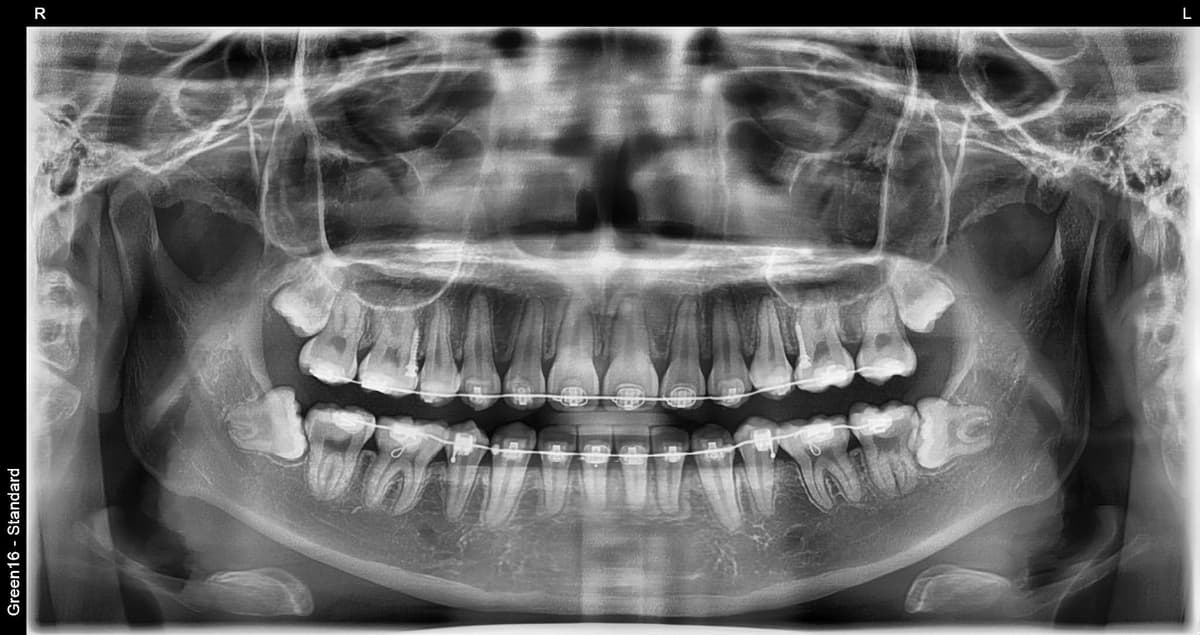

复杂的阻生智齿 - 即使深埋在牙龈中也没问题

贴近神经的智齿 - 无需担心神经损伤,安全拔除

水平阻生智齿 - 即使是横向生长的困难案例也可以处理

凭丰富的拔牙经验,

安全解决疑难案例